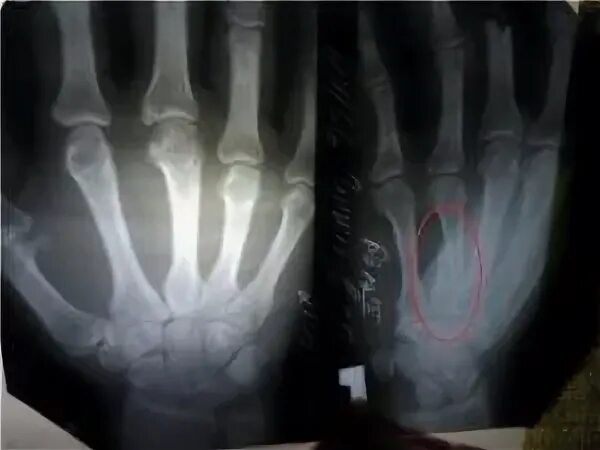

Чтобы быстрее сросся перелом руки